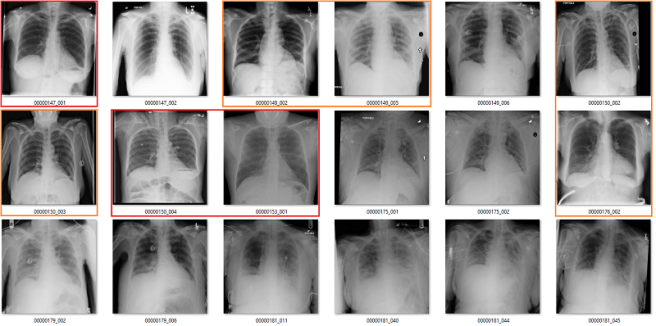

Effusion

In this case, the blue labels mean there is significant lung disease present.

An effusion is fluid in the space around the lung. The list of causes is a mile long, but the two main groups are effusions caused by pleural disease, and those caused by lung disease.

It is not clear to me what it means to identify effusions that exist with significant lung disease. In many of these cases, it is not even really possible to visually identify the effusion, we just know that an effusion must be present so we describe it. See the last three images in the picture above for a good example of this. The main pathology in those cases is consolidation, in my opinion.

I can see value in identifying small, isolated pleural effusions. There are about a half dozen examples of these above, including the first and third images. There isn’t any lung disease to suggest the cause of effusion, which makes the effusion itself significant.

I could also see the benefit in identifying large effusions that might need intervention (like draining them with a needle). The 10th image is an example of this.

So it isn’t really clear to me what this label means. Without a guiding philosophy based in clinical practice, it isn’t very useful.

Pneumothorax

A pneumothorax is when there is air in the pleural space around the lung. This can cause the lung to collapse, and is a pretty serious finding. They can be really subtle on x-rays and are often missed.

At first glance, the labels look good. In these 18 cases, only the one highlighted in orange is a bit questionable, and that may just be because I am not looking at the image in diagnostic conditions.

But the green boxes are a problem. These are cases of pneumothorax where the patient has already been treated with a chest drain. There are two issues here:

- This isn’t a medically important problem. We want to avoid missed pneumothoraces, and by definition these have not been missed.

- If so many of the images have chest drains, an AI system will probably learn to identify chest drains instead of pneumothoraces. It is entirely likely that the majority of image batches the model sees will contain no pneumothorax without a chest drain.

Fibrosis

We already saw above that the fibrosis labels are low accuracy, even being generous. But again, the problem is worse. In this image, the reds are incorrect labels, but the orange labels are where I have no idea. There are pleural effusions and/or consolidation. Could there be fibrosis under that? Sure, but there is no way to tell on these pictures.